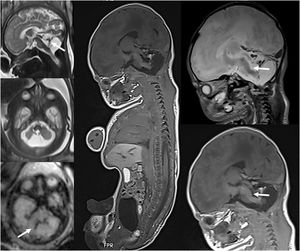

A)Ecografía transfontanelar realizada en el primer día de vida en neonato a término con hipoxia-isquemia grave que demuestra lesión bilateral de sustancia gris central (flechas). B)RM craneal realizada a los 4días de edad que demuestra lesión bilateral de sustancia gris central en las secuencias T1, T2, con restricción en difusión, con evidencia de perfusión elevada en ASL (flechas), lo cual se ha correlacionado con mal pronóstico.